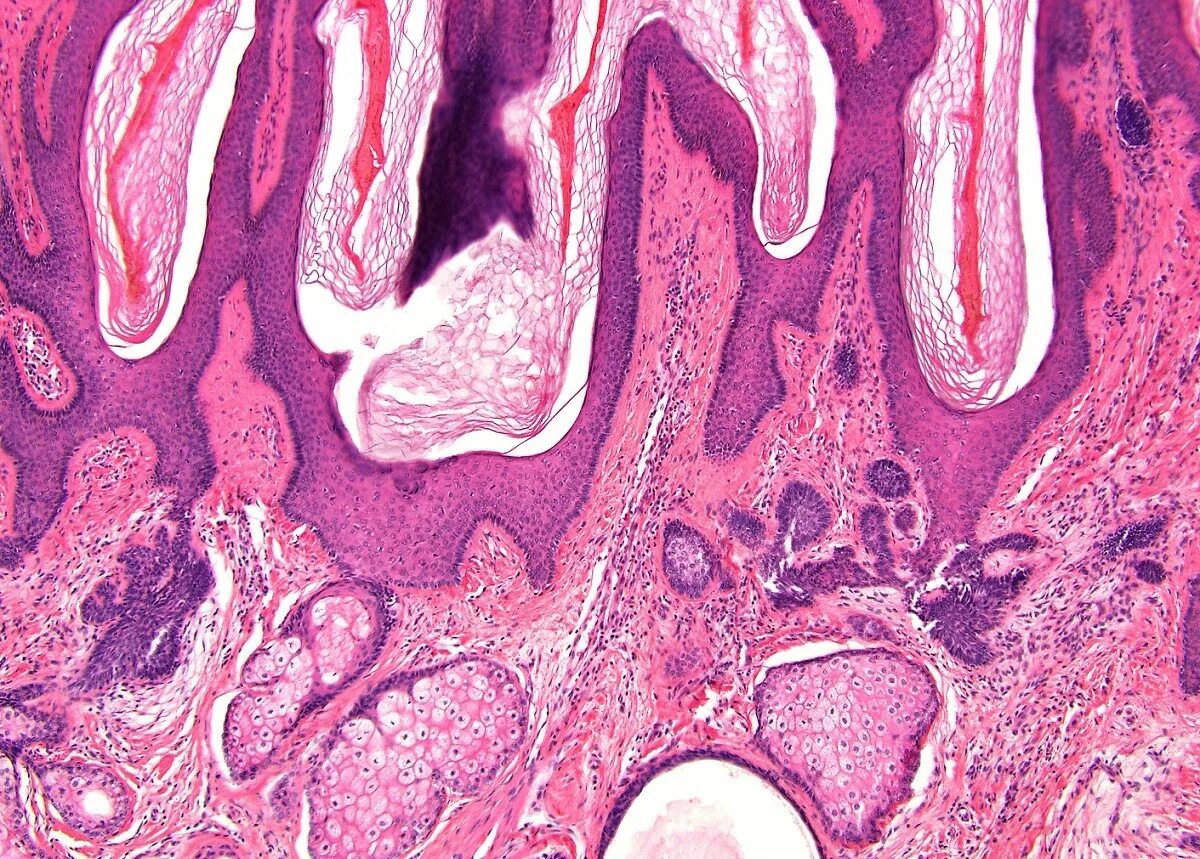

Гистология сложная